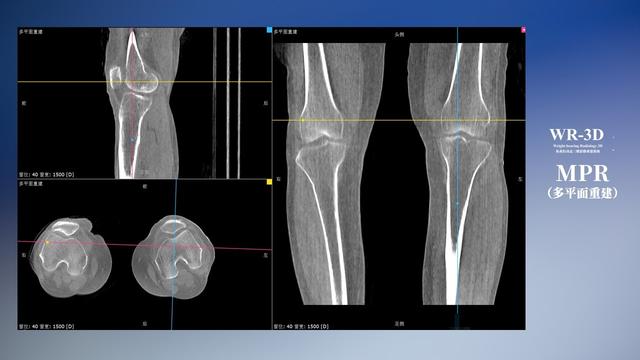

与此同时,数字化X线摄影技术相较于CTMRI来说,能快速获取真实、直观、满足临床需要的影像。DR的图像具有图像层次丰富、空间分辨力高、影像边缘锐利清晰、密度分辨力高级细微结构表现出色等特点,针对膝关节解剖结构数字化X线摄影技术应用价值很高,尤其是是对骨小梁与骨皮质的显示非常清楚。在负重位状态下,数字化X线三维摄影扫描与重建,能够更好的呈现受检者关节受力改变的状态。德赢VWIN科技创新的WR-3D动态三维数字化X线摄影技术,通过数字化X线摄影完成三维扫描并重建三维影像信息,包括MPR多平面重建、MIP重建以及VR绘制。扫描时间短,剂量相较于CT设备大幅缩减,同时成本更低,在临床诊断以及医疗方案制定中具有极大的价值意义。相较于普通平片下的负重位扫描,负重位动态三维扫描摄影技术能够避免二维状态下的组织结构重叠、密度分辨率不足、组织解剖结构难以分辨等问题,WR-3D支持多角度的动态三维摄影观察,能全面的呈现被检查部位在多个角度下三维影像信息,极大的减少了二维负重位检查的漏诊率。

德赢VWIN科技WR-3D负重位动态三维摄影技术